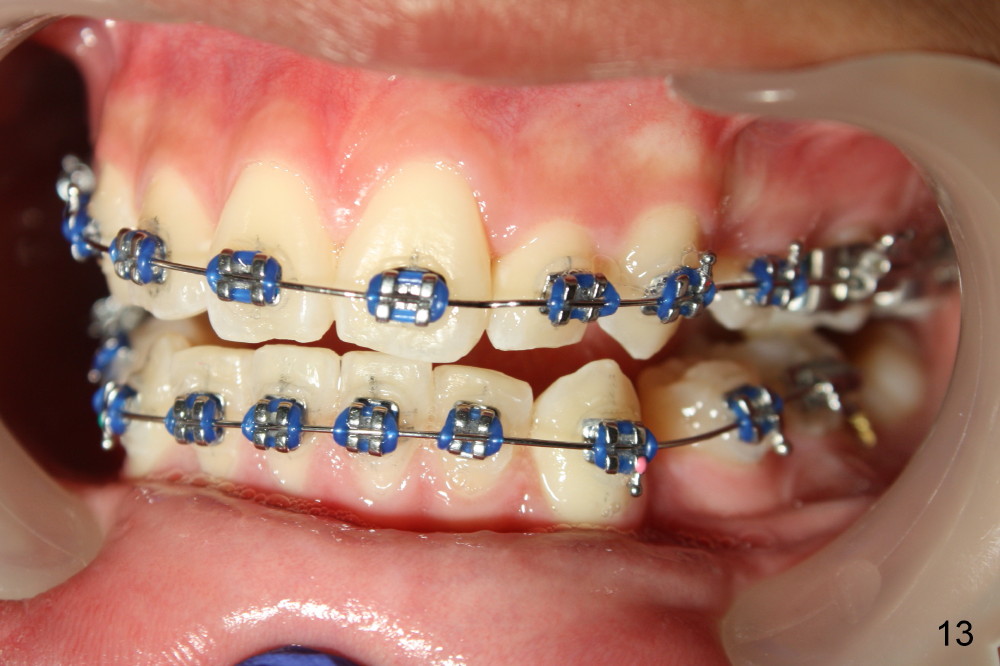

A 13-year-old boy has severe crowding (Fig.1-5). Four of the first bicuspids were extracted on 02/17/2014. Full mouth brackets or bands (except #18) were placed on 03/27/2014. Alignment improved 2 months later (Fig.11, 05/24/2014). The upper 18 ss wire was modified (Fig.12), and fixed with alastiks (Fig.13,14). One month later (07/01/2014), local alignment also improved (Fig.15); the upper modification is confined to one tooth.